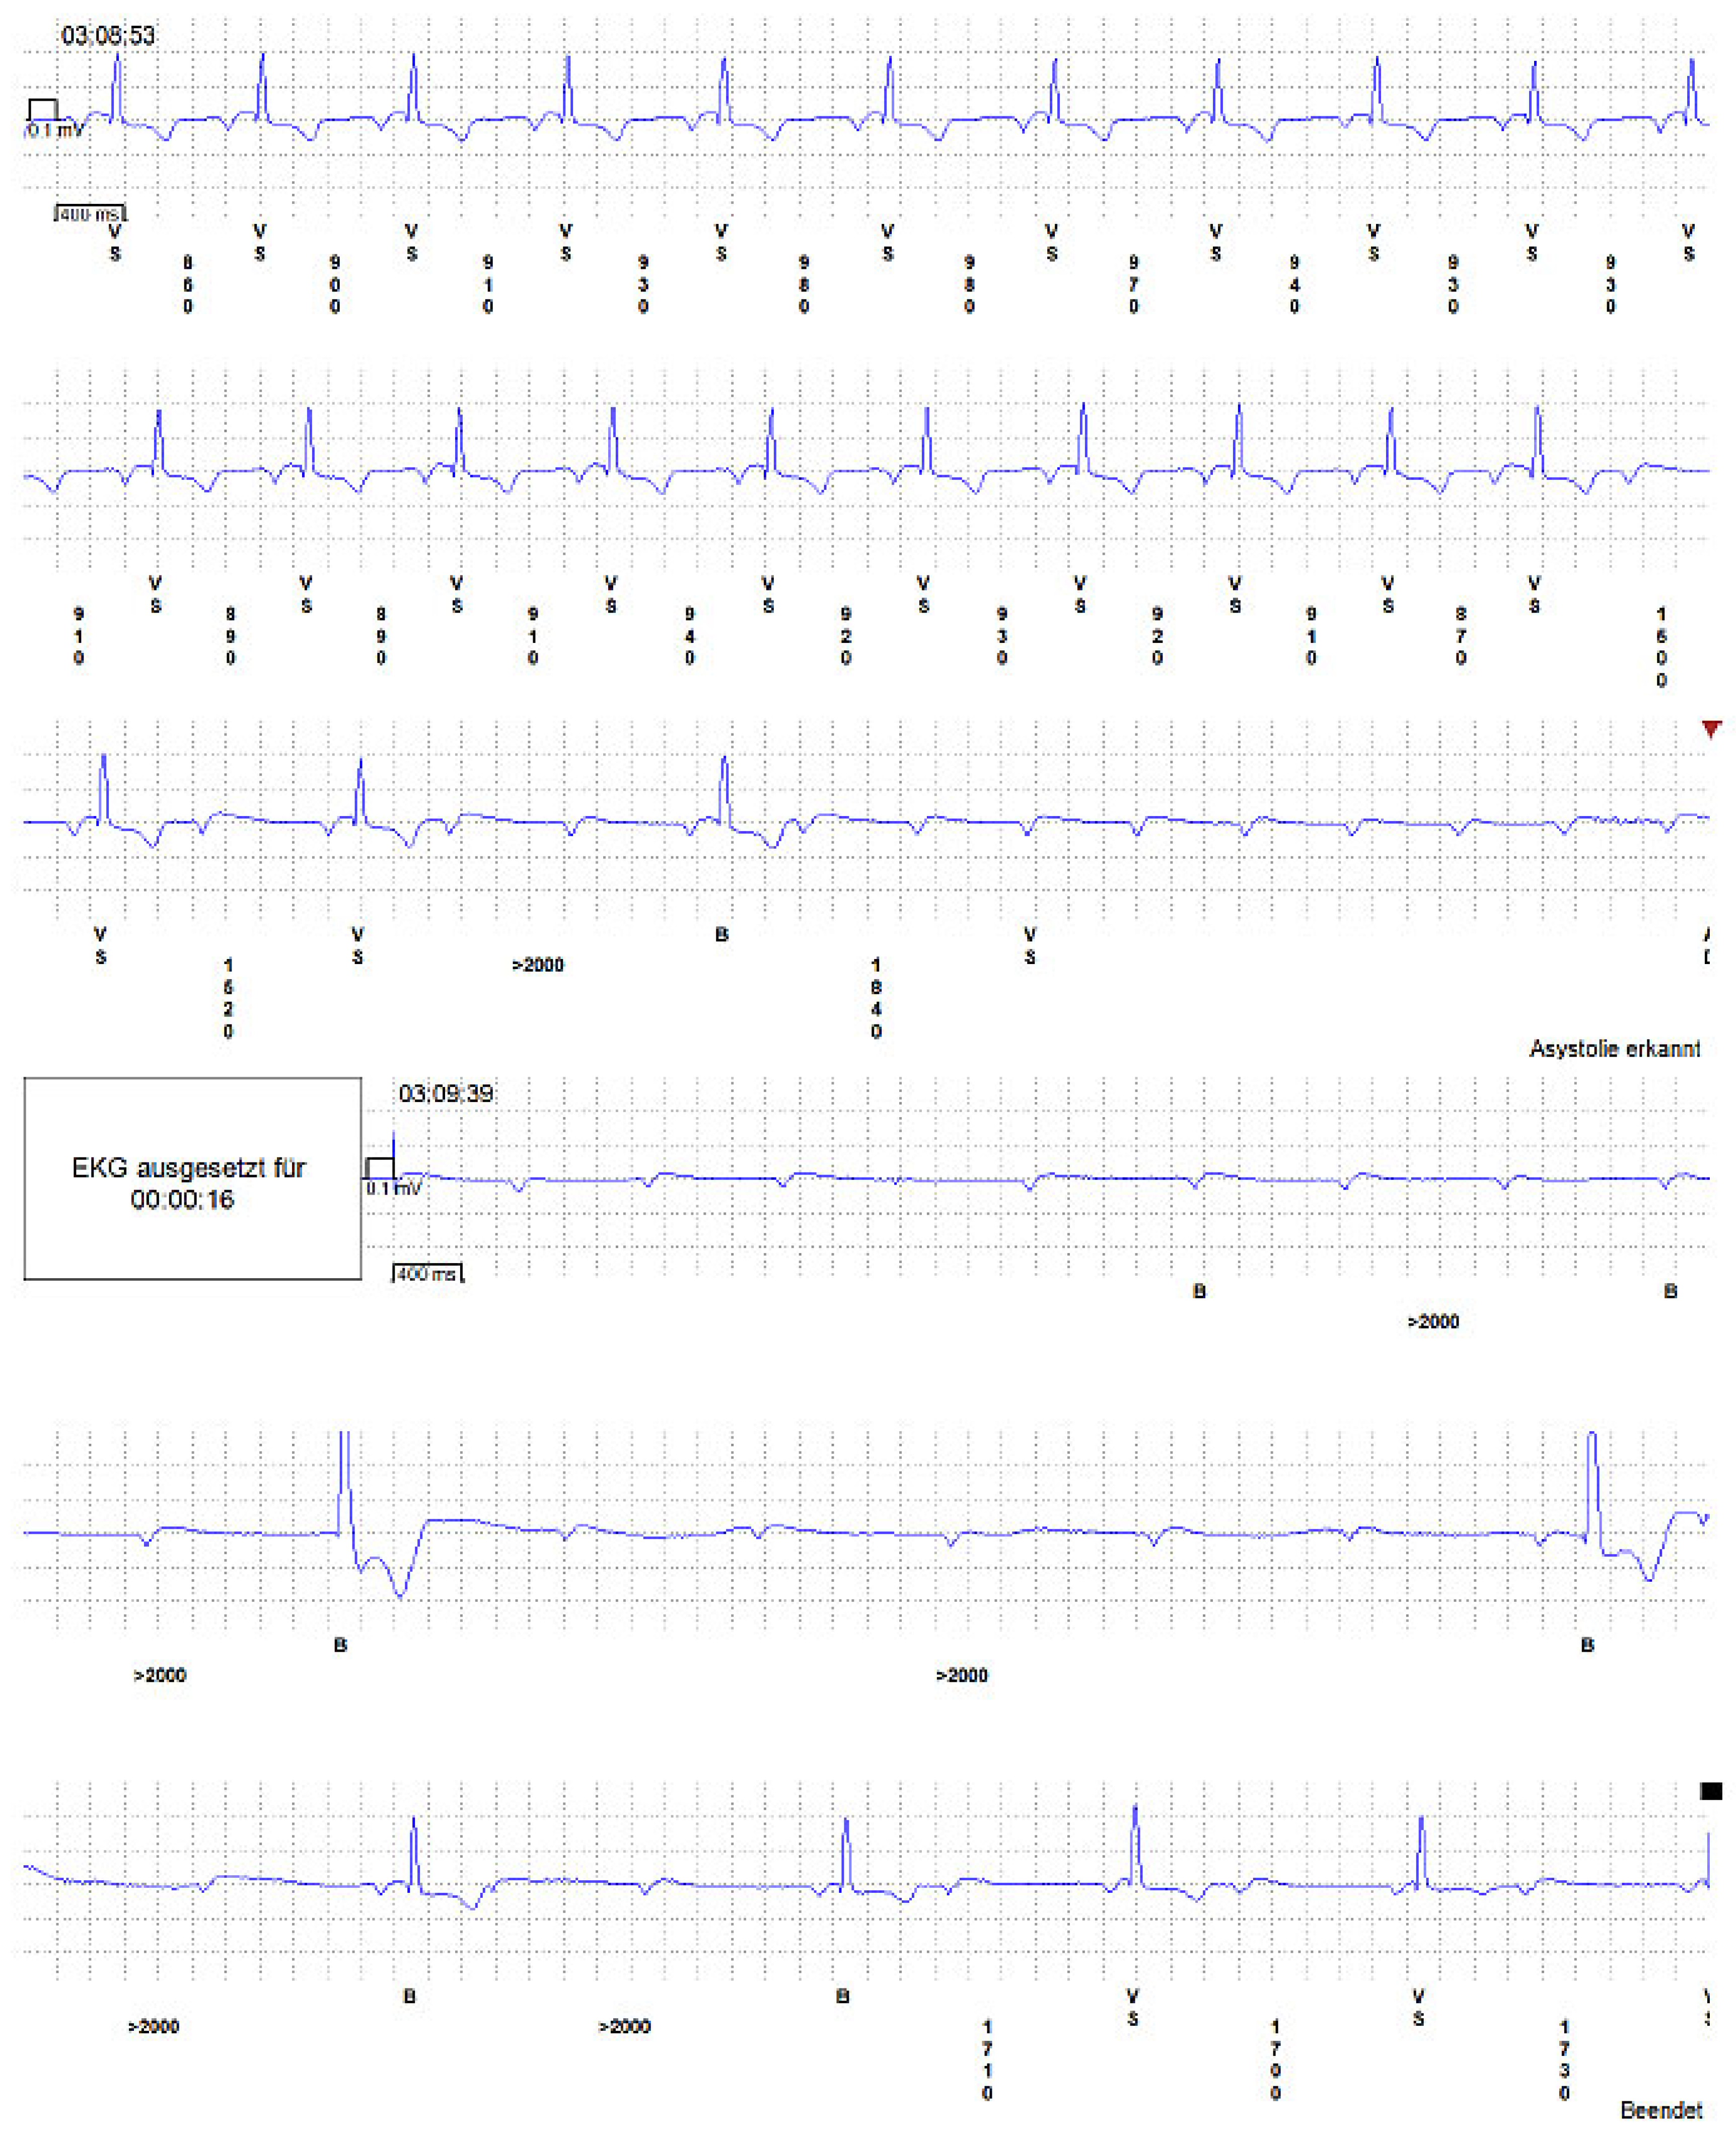

Figure 6. One of the automatically transmitted episodes, showing complete atrioventricular block for over 16 seconds with an insufficient ventricular escape rhythm.

Some 6 weeks later, several automatically generated episodes were transmitted via the internet (Figure 6). An urgent telephone follow-up revealed that the patient was suffering from (yet another) episode of diarrhoea and vomiting, and had suffered five syncopal events. In total, 10 episodes of ventricular asystole were recorded, the longest for 30 seconds, which explained the patient’s syncopal events. She was admitted urgently to hospital and, after cure of the viral gastroenteritis, a dual-chamber pacemaker was implanted and the ILR explanted without any complications.